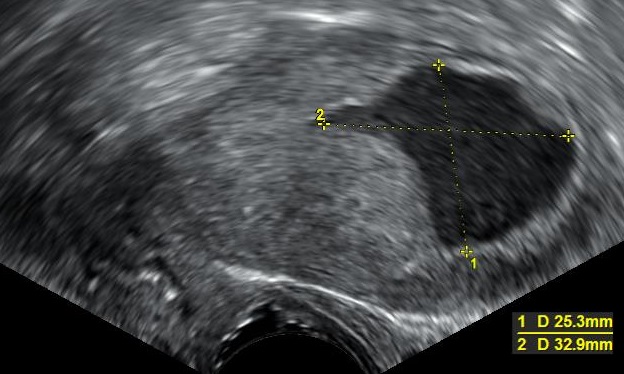

자궁내막암 진단은 신체 검사, 자궁내막 생검 또는 자궁내막 소파술(D&C)을 통해 이루어진다. 이 조직은 암의 특징을 확인하기 위해 조직학적으로 검사한다. 암이 발견되면, 암이 근층(자궁의 근육 벽)이나 자궁 경부와 같은 조직으로 전이되었는지 또는 침투했는지를 확인하기 위해 의료 영상 검사를 수행할 수 있다.[9] 2024년의 한 연구에 따르면, 질식 초음파 검사는 근층 침윤 평가와 관련하여 자기 공명 영상(MRI)과 유사한 진단적 성능을 제공한다. 그러나 자기 공명 영상은 저등급 자궁내막암에서 유의하게 더 나은 특이성을 보였다.

폐경기 자궁을 보여주는 초음파 이미지로, 자궁내막암이 매우 의심되는 소견이다">

자궁내막암이 발견되면 암의 확산 및 조직 침범 여부를 확인하기 위해 의료 영상 검사를 수행한다. 2024년 연구에 따르면 질식 초음파 검사는 근층 침윤 평가에 있어 자기 공명 영상(MRI)과 유사한 진단적 성능을 제공하지만, MRI는 저등급 자궁내막암에서 더 나은 특이성을 보였다.[37]폐경기 출혈이 있는 여성의 경우, 질식 초음파 검사를 통해 자궁내막 두께를 검사하는 방법이 자궁내막암 진단에 많이 사용된다. 영국에서는 자궁내막 생검과 질식 초음파 검사를 함께 사용하는 것이 표준 진단법이다. 질식 초음파 검사에서 보이는 조직의 균질성은 암성 여부를 판단하는 데 도움이 되지만, 초음파 소견만으로는 결정적이지 않으므로 자궁내막 생검과 같은 다른 검사 방법을 함께 사용해야 한다.

폐경기 출혈이 있는 여성의 자궁내막 두께를 검사하기 위한 질식 초음파 검사는 미국에서 자궁내막암 진단을 돕기 위해 점점 더 많이 사용되고 있다.[37] 영국에서는 자궁내막 생검과 질식 초음파 검사를 함께 사용하는 것이 자궁내막암 진단의 표준 치료법이다.[35] 질식 초음파 검사에서 보이는 조직의 균질성은 두께가 암성인지 여부를 나타내는 데 도움이 될 수 있다. 초음파 소견만으로는 자궁내막암의 경우 결정적이지 않으므로 다른 선별 검사 방법(예: 자궁내막 생검)을 함께 사용해야 한다. 다른 영상 검사는 제한적으로 사용된다. CT 스캔은 신체 검사에서 진행된 것으로 보이거나 고위험 아형(전이 위험이 높은)을 보이는 종양의 수술 전 영상 검사에 사용된다.[38] 또한 골반 외 질환을 조사하는 데에도 사용할 수 있다.[35] MRI는 암이 자궁 경부로 전이되었는지 또는 자궁 경부 선암종인지 확인하는 데 어느 정도 도움이 될 수 있다.[38] MRI는 또한 인접 림프절을 검사하는 데 유용하다.[35]